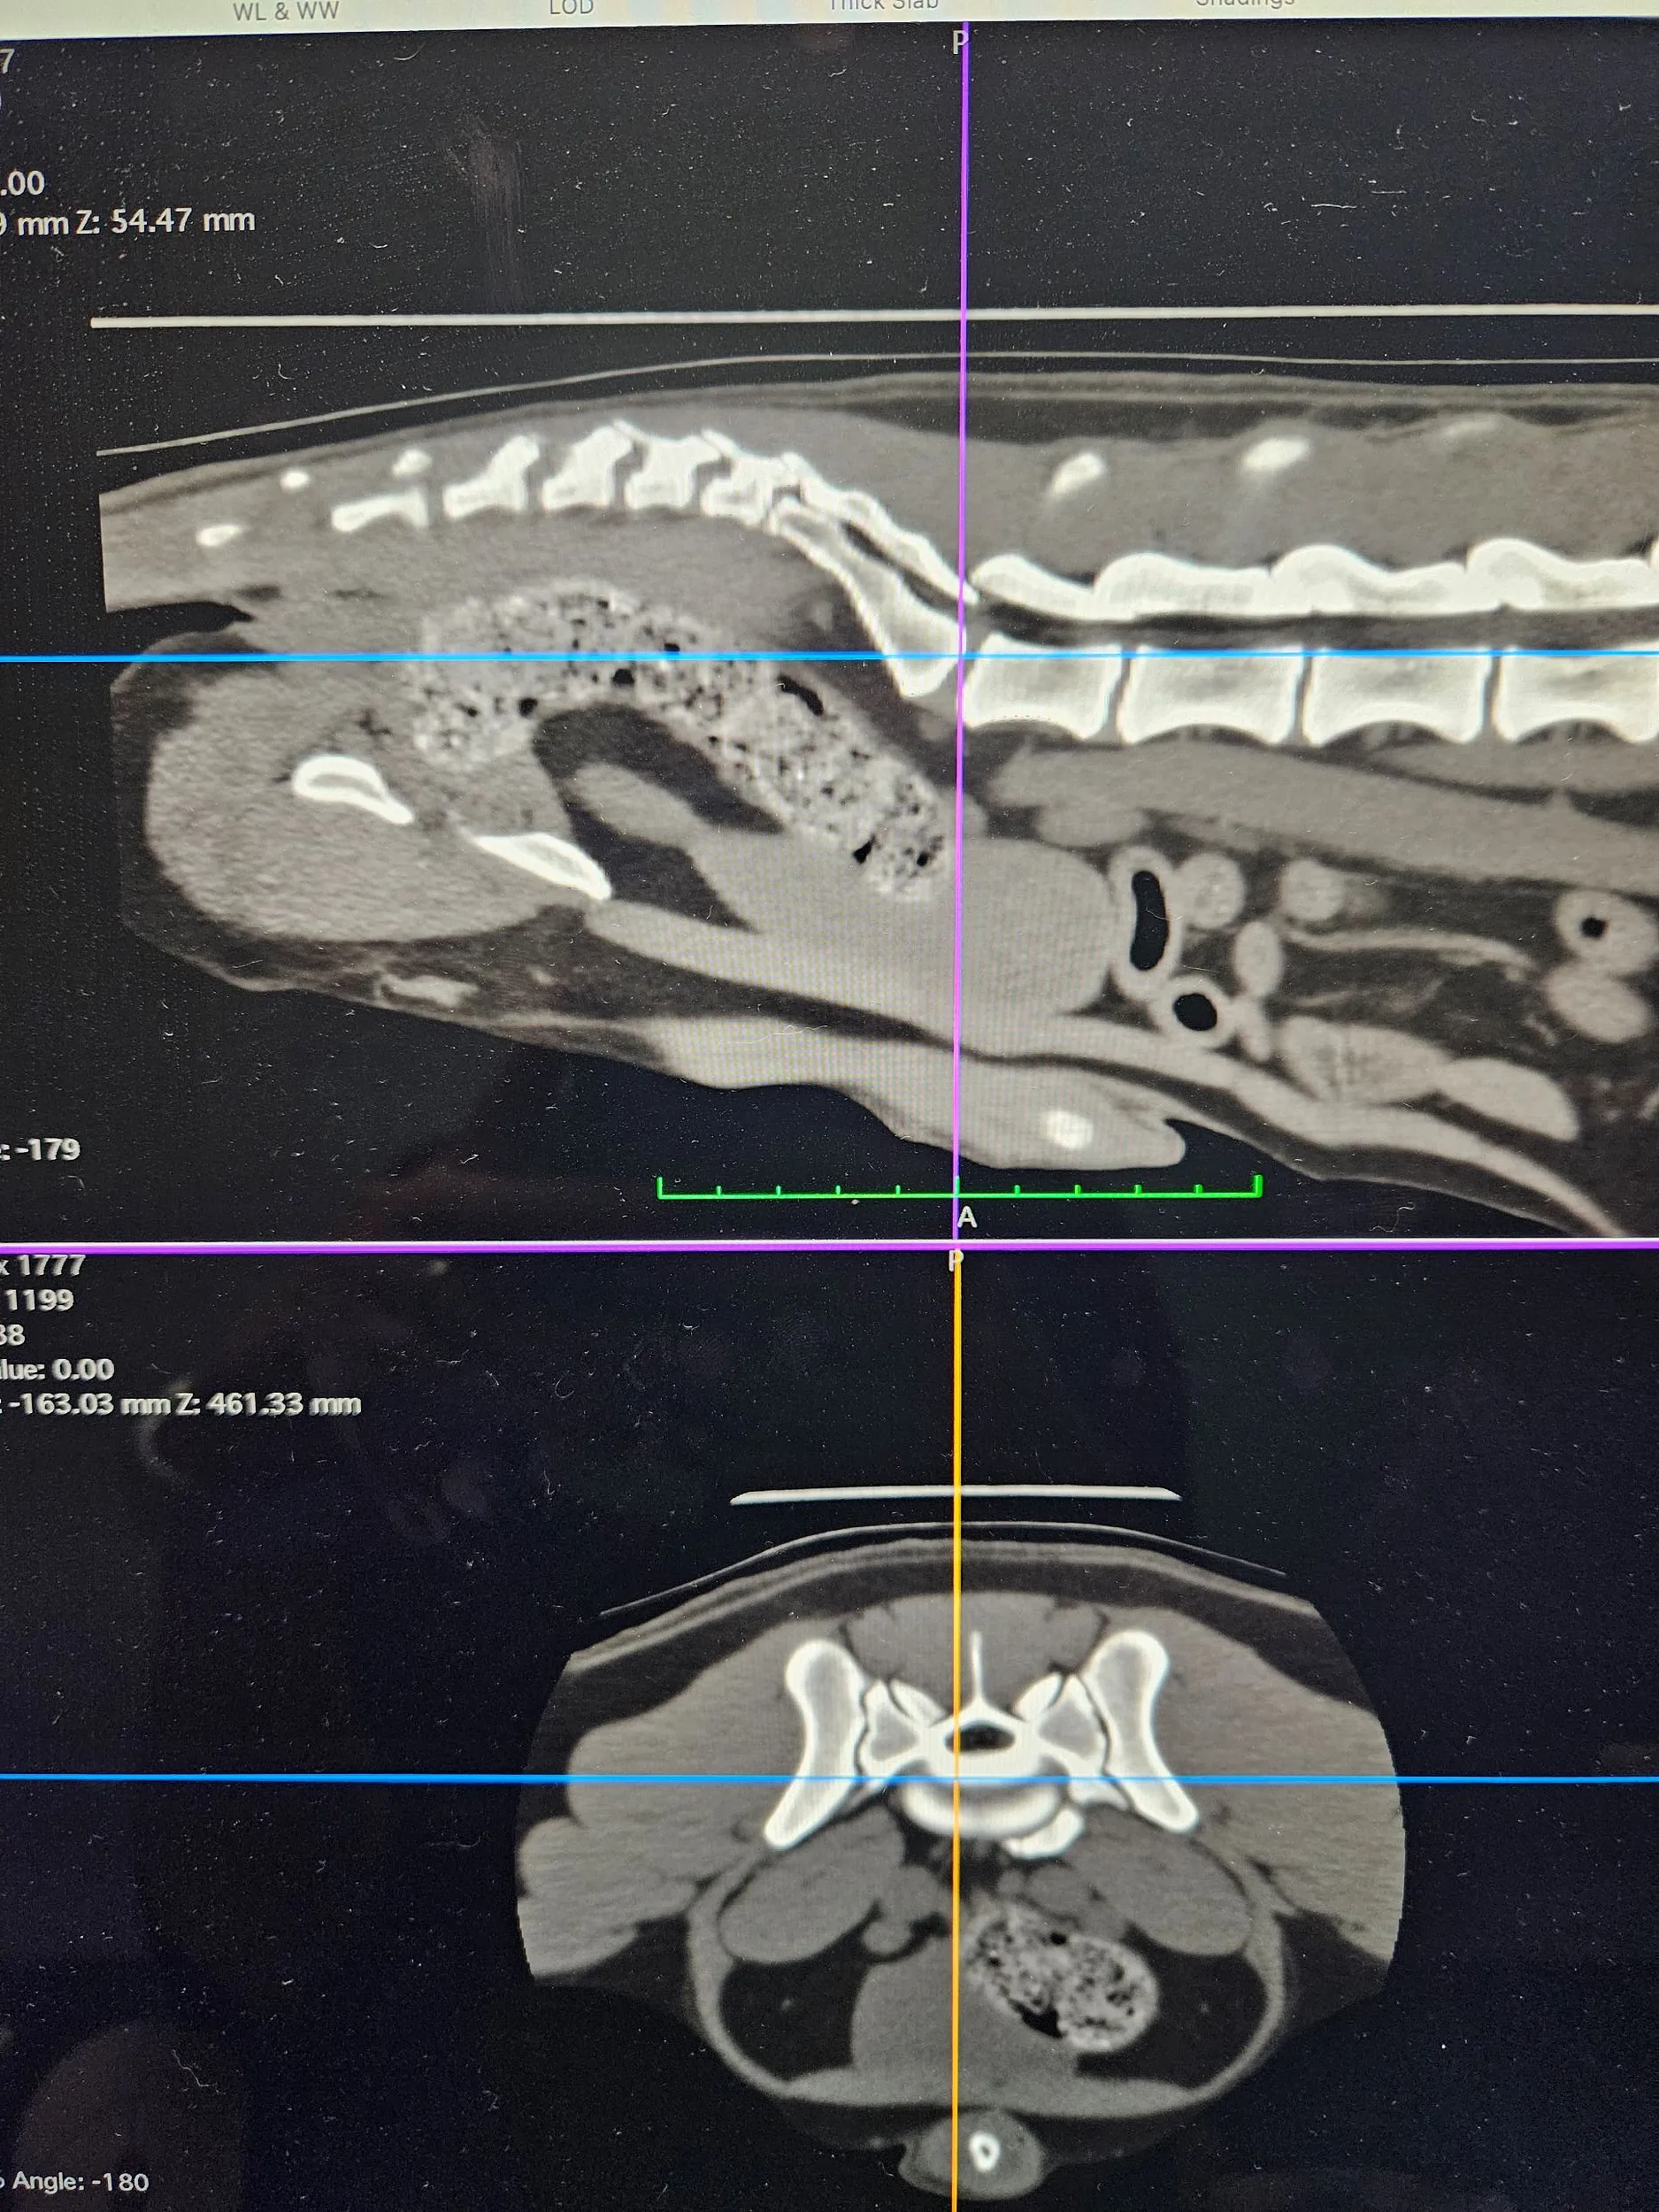

CT Scanner

Our CT scanner was installed at our Tunstall practice in 2017 and was the first permanent veterinary CT scanner in our area. It is available 24 hours a day to both our own patients and as a referral service to surrounding practices.

Computed Tomography (CT) involves the use of x-rays to take thousands of pictures of cross-sections of the body. These can then be built up into a 3D image and used to create a detailed reconstruction of the patient. This is a thorough and prompt way to reach a diagnosis and enable quicker treatment. The CT scanner is particularly useful for the diagnosis and planning of complex surgical procedures and medical conditions.

We are able to obtain full results from external specialists and also, we are lucky that one of our own vets - Charlie Green - is an Advanced Practitioner is Diagnostic Imaging and a General Practitioner in CT; meaning she can read our CT scans on site and enhance surgical planning and treatments.

Brian’s CT Scan

The first CT scan we carried out was done on Clive's dog, Brian's, nose. We found a sarcoma in his upper jaw, and successfully removed it. A CT was needed to ensure the surrounding area was in good health.